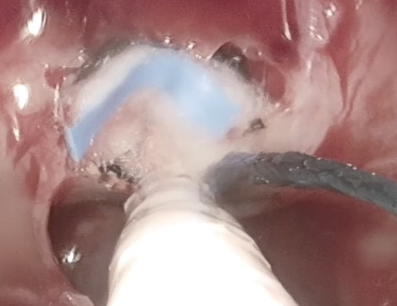

Μικροαδενώματα που δεν προκαλούν συμπτώματα δεν είναι αναγκαίο να χειρουργούνται, αρκεί η παρακολούθηση τους με μαγνητικές τομογραφίες, οφθαλμολογικές και ενδοκρινολογικές εξετάσεις ανα τακτικά χρονικά διαστήματα. Στην περίπτωση των μακροαδενωμάτων, που συνήθως, προκαλούν περιορισμό των οπτικών πεδίων και υπολειτουργία της υπόφυσης ή σε περίπτωση αδενωμάτων γενικότερα με υπερέκκριση ορμονών προκρίνεται η χειρουργική θεραπεία. Αυτή διενεργείται στην πλειονότητα των περιστατικών ενδοσκοπικά ή μικροχειρουργικά διαρρινικά χωρίς εμφανή τομή (εικόνα 1).

Μία από τις πιο συνηθισμένες παθήσεις στο κρανίο στην οποία χρησιμοποιείται το ενδοσκόπιο είναι οι όγκοι του τουρκικού εφιππίου, όπως τα καλοήθη αδενώματα της υπόφυσης και τα κρανιοφαρυγγιώματα. Στις περιπτώσεις αυτές η είσοδος στο κρανίο γίνεται από την μύτη (Εικ. 1). Το ενδοσκόπιο παρέχει εξαιρετική απεικόνιση της περιοχής από τον βλεννογόνο της μύτης μέχρι και τον σφηνοειδή κόλπο και την περιοχή της υπόφυσης μετά το άνοιγμα του εδάφους του τουρκικού εφιππίου. Αντιπροσωπευτικές διεγχειρητικές φωτογραφίες φαίνονται στις εικόνες 2α,β,γ.